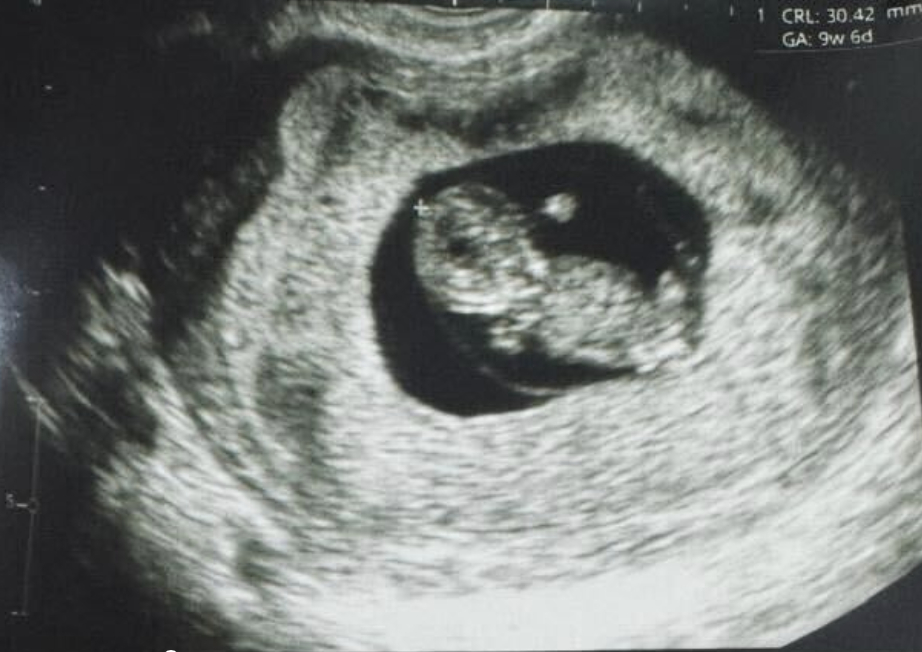

嬰兒的放射線圖像